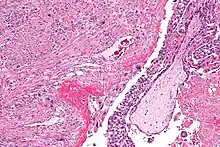

Môle hydatiforme complète

La môle hydatiforme complète survient lorsque l’ADN de la mère disparaît complètement après la fécondation et qu’il y a doublement de l’ADN du père. En l'absence d'ADN maternel, le fœtus ne se forme pas et un tissu ressemblant à une grappe de raisin se développe.

Un fœtus normal peut se développer à côté d’une môle hydatiforme.